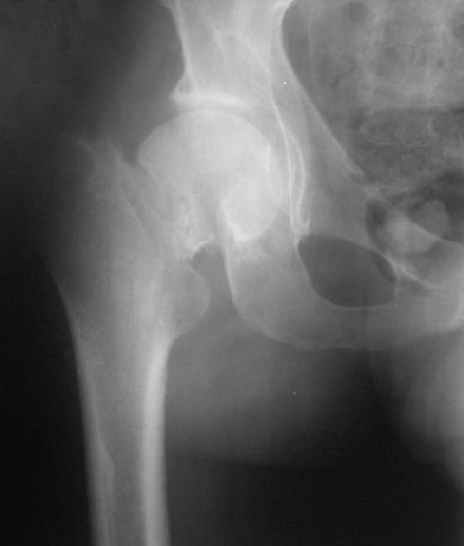

Нелеченный перелом шейки бедра / Neglected femoral neck #

Однако на сегодняшнем снимке обнаружился перелом шейки бедра. Больной уже ходитс частичной нагрузкой. Учитывая срок и картину на снимке, что предпринять? У нас предложены варианты 1)не оперировать, 2)закрыто 2 спонгиозных винта, 3)вальгизирующая остеотомия. Эндопротез как-то даже в список включать пока не хочется. Какие есть соображения? Что из перечисленного или что-то другое выбрать и почему? Заранее спасибо.

Dear colleagues,A male 31 years old treated elsewhere after not severe pelvic fracture, was managed non operatively. So the injury looked as a reason of his inability to elevate the leg. However at the recent x-rays the neck fractire was found. The patient already has been walking with partial weight-bearing.Looking at the x-rays and the time since the injury, what is the optimal treatment for now? We discussed 1)leave as is, 2)2 cancellows screws as is, 3)valgus osteotomy. Total hip replacement looks unnecessary yet.What is your opinion? Which option from the listed or something else should be preferred and why?THX in advance.

При явно выраженном варусе и флексионных состояниях после сросшихся переломов шейки бедра у молодых рекомендуется реконструктивная операция по исправлению варуса для предотвращения раннего деформирующего артроза, приводящего в результате переднего импинжмента, как показано на снимке.

Межвертельная вальгусная остеотомия представляет наименьший риск среди всех реконструктивных операции в проксимальной части бедра, создавая наилучшие биомеханические условия (увеличивается сила абдукторов, увеличивается сила суставной реакции, уменьшение рычага моментов абдукторов и уменьшение скольжения) и при меньшем риске повреждения кровоснабжения головки, где обычно в 90% случаях достигается отличный результат при применении метода для лечения ложных суставов шейки бедра.

Из 14% осложненных после перелома шейки нуждаются в коррегирующих или восстановительных операциях. В данном случае речь не идет о сращении перелома, а задача состоит в том, что необходимо предотвратить осложнения после сращения, даже небольшая сгибательная деформация на шейке (на боковом снимке) и варус впоследствии могут создать большую проблему по импинжменту и образованию раннего артроза.